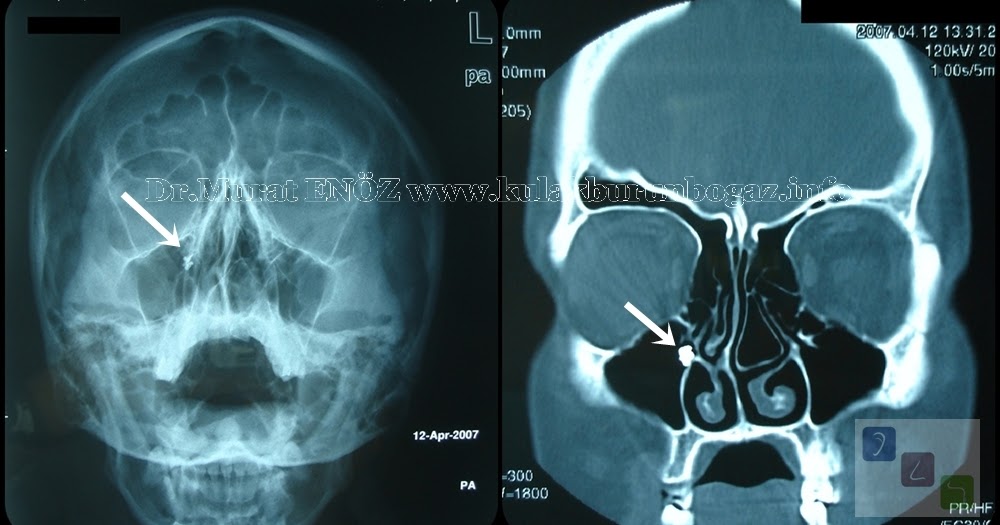

From www.ent-istanbul.com

Tooth Filling Material (Amalgam) in the Maxillary Sinus Amalgam Fillings And Sinus Problems some of the mercury vapour from amalgam fillings adheres to the lining of the nose and sinuses from where it can be transported. it has been established that dental amalgam fillings may lead to local adverse reactions, including oral lichenoid reactions (21), and. cnn — the us food and drug administration warned thursday that silver dental fillings,. Amalgam Fillings And Sinus Problems.